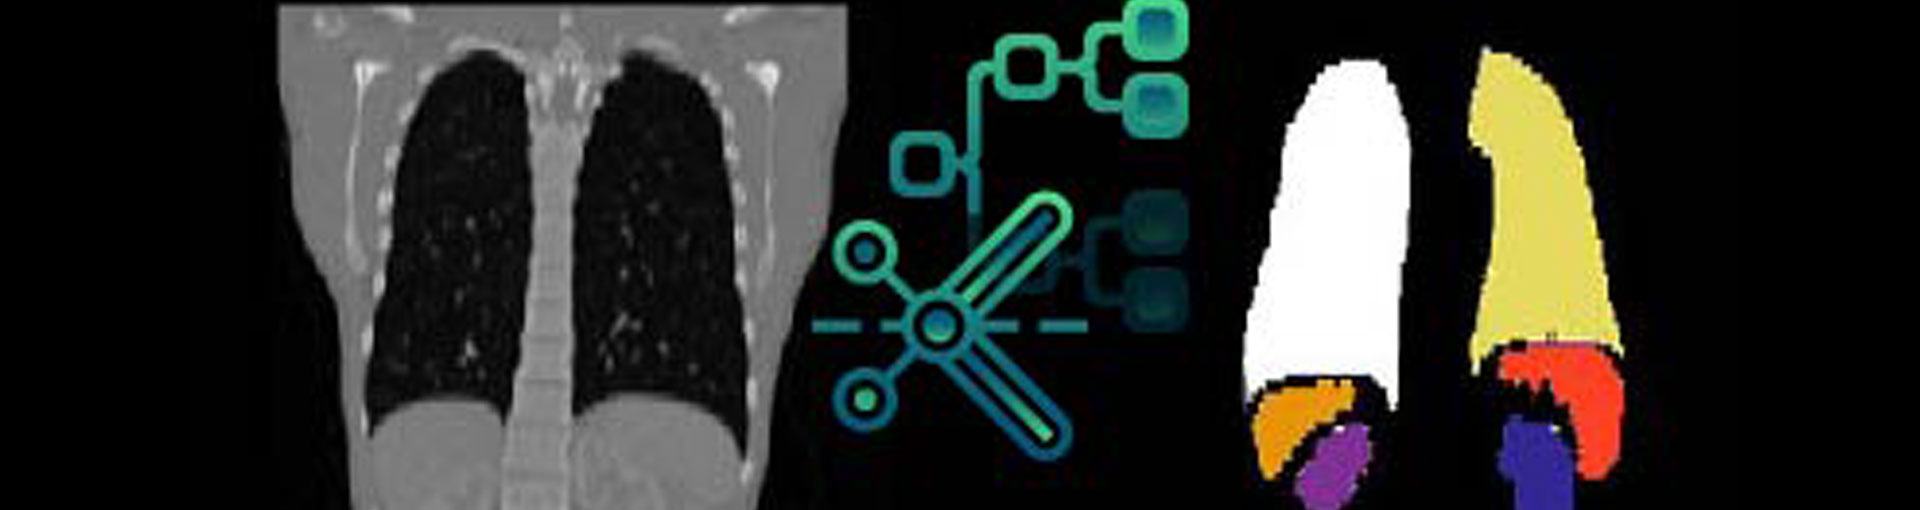

AI models for clinical and preclinical questions

We develop AI models based on high-quality annotations that help identify relevant patterns in image data and support clinical decision-making processes. Our focus is on robust algorithms that are developed and validated in accordance with regulatory requirements.

The combination of deep learning, structured data analysis, and interactive visualization allows researchers and clinical teams to use large image datasets more efficiently. This is essential for addressing issues related to liver disease, whether in clinical studies, translational research, or the development of image-based diagnostic tools.